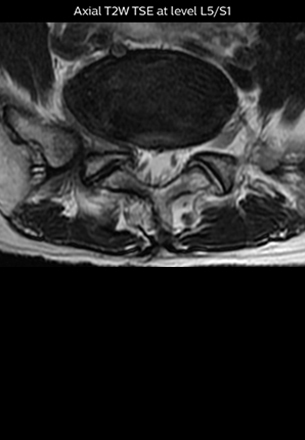

“In patients with lower extremity neurological symptoms, NerveVIEW helps us to determine the disease matching the patient’s symptoms by directly visualizing the nerves. We use the sequence mainly, when there is suspicion of intraforaminal stenosis, extraforaminal stenosis or lateral disc herniation, which is often based on routine T2- and T1-weighted images. Additionally, the excellent depiction of the course of nerves makes NerveVIEW a good navigator when applying treatment such as block therapy or surgery.”

The key concept in MR neurography, Dr. Yabuki stresses, is the ability to directly visualize spinal nerves, versus inferring the presence of pathology indirectly. “Before NerveVIEW, we estimated compression of the nerve by looking for the presence or absence of fat signal on other MR images,” he says.

“For example, in sagittal images, when the presence of fat is observed in the intervertebral foramen, it suggests that there is a margin around the nerve. Similarly, the absence of fat indicates that the nerve is being compressed. So, we used to deduce nerve compression indirectly. With NerveVIEW, however, we can observe the condition of the nerves directly, regardless of the presence or absence of fat. We always prefer such direct observation of anatomy over having to make an inference about it.”

“The intra-luminal signal of veins, especially around the intervertebral space, can be suppressed well with NerveVIEW. As a result, we can easily observe the detailed nerve structure around the posterior ganglion,” he says. “This is why we use 3D NerveVIEW for intraforaminal stenosis and extraforaminal stenosis/herniation (lateral disc herniation). On the other hand, if herniation is suspected to exist inside the dorsal root ganglion (DRG), balanced TFE or ProSet-FFE is applied. NerveVIEW is not suitable for evaluating the median type of herniation.”